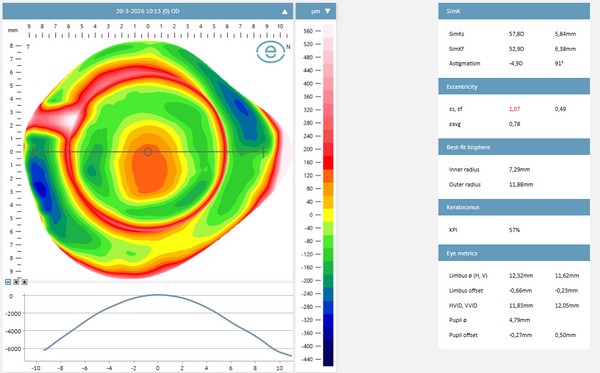

ESP Eye Surface Profiler

De ESP Eye Surface Profiler maakt een gedetailleerde 3D-kaart van het volledige oogoppervlak — hoornvlies én sclera. Deze meting geeft inzicht in de exacte contour van de sclera, inclusief asymmetrie en onregelmatigheden. Op basis hiervan wordt de scleraalens geselecteerd of besteld met de juiste landing-zone parameters.

Zonder ESP-meting is scleralensaanpassing grotendeels trial-and-error. Met ESP wordt het aanpassingsproces aanzienlijk efficiënter en nauwkeuriger — minder proeflenswisselingen, beter eindresultaat.

Een indicatieve oogmeting en een uitgebreid onderzoek met de biomicroscoop (spleetlamp) is de eerste stap. De bolling, kromming en afvlakkingen van de oogbol en de sclera worden bepaald. Een topograafmeting geeft direct een indicatie van een onregelmatige cornea, zoals bij keratoconus. Aanvullend wordt een voorsegment-oogscan gebruikt om diepere lagen, zoals de achterzijde van het hoornvlies, te bekijken.

De meetgegevens van de ESP worden verwerkt in een speciale database. De eerste ideale aanpassing wordt direct zichtbaar en de optometrist kan de lens op alle punten aanpassen.